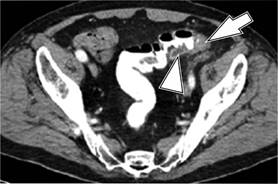

El estadio de la enfermedad en pacientes con diverticulitis a menudo se determina mediante el sistema de clasificación de Hinchey modificada por Wasvary (1999) y los hallazgos tomográficos por Kaiser a los que se incorporan los resultados de imagen (Cuadro 1 y Figura 1),16 los cuales comprenden desde el estadio 0 hasta el IV, en los que el estadio 0 (Figura 2) nos habla de una diverticulitis clínicamente moderada. El estadio I se divide en dos el IA (Figura 3) que se refiere a la inflamación pericólica limitada sin absceso y el estadio IB (Figura 4) en el que además de inflamación hay absceso adyacente a la zona de inflamación. En el estadio II (Figura 5) se encuentra el absceso pélvico, retroperitoneal o a distancia. En el estadio III (Figura 6) evoluciona a peritonitis generalizada sin comunicación a la luz intestinal y en el estadio IV hay peritonitis fecaloide con comunicación a la luz intestinal.17,18

Figura 5: Diverticulitis grado II: TC corte axial muestra engrosamiento de la mucosa (cabeza de flecha) así como absceso pélvico (flecha).